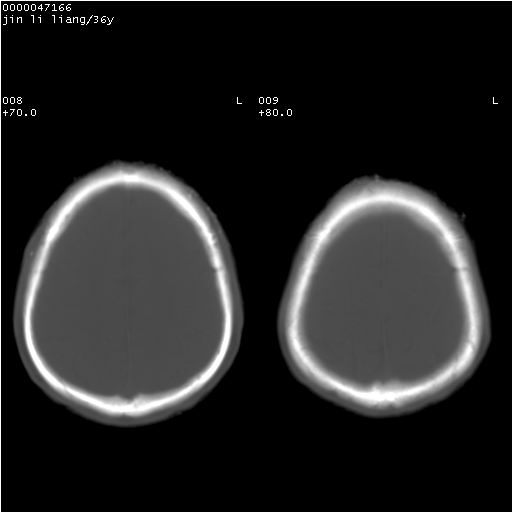

患者 男,36岁。头面部“土炮”炸伤。pe:面目全非,伤口流血不止。

临床诊断:头面部外伤。

颅脑ct轴位平扫(层厚、层距均为10mm),图像如下: